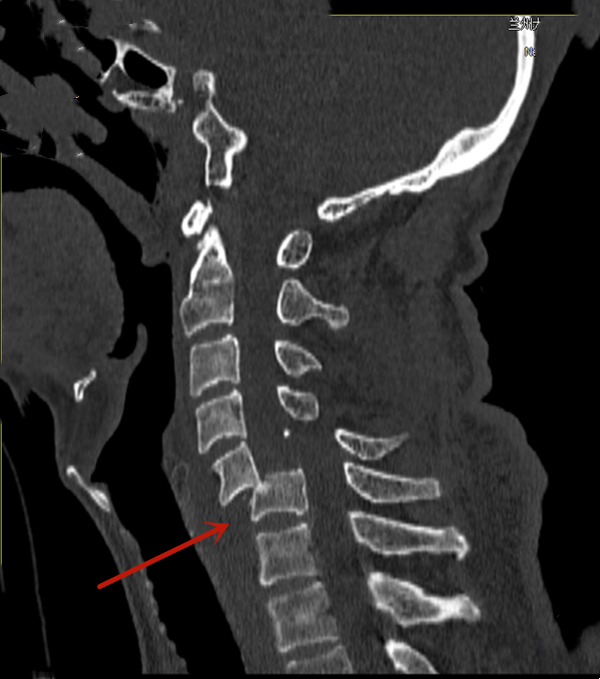

颈椎骨折脱位

左肩部疼痛,左上肢无力14小时"入院,辅助检查示第3颈椎体脱位,颈3/4